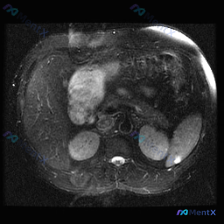

今天整理了一个挺有意思的影像读片病例,有点「答非所问」但非常考验临床思维,和大家分享一下思路。 --- 病例背景与影像资料 用户明确问的是「脾脏病变」,提供的是一张腹部MRI-T2加权轴位图像。 先直接说针对「脾脏」的第一判断: 👉 在这张图像上,脾脏实质信号均匀,皮髓质分界清晰,没有看到局灶性的高...